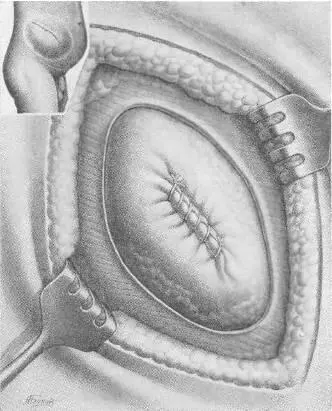

Объективно: больной — тучный мужчина, высокого роста, вес 102 кг. Послеоперационный рубец длиной 20 см. Грыжевое выпячивание размером 20 Xl5 Xl см, вправляется с трудом. На рентгеноскопии в грыжевом мешке обнаружены петли тонкой и сигмовидной кишок. Операция под эфирно-кислородным наркозом. Из рубцово-измененных тканей с трудом выделены края грыжевого дефекта (16x10 см). Петля тонкой кишки сращена со стенкой грыжевого мешка. Спайки разделены. Грыжевой мешок ушит (рис. 107 а). Произведена пластика путем подшивания двух листков капроновой сетки к краям дефекта передней брюшной стенки (рис. 107, б, в, г) [32]. Над верхним листком капрона зашита подкожная клетчатка. Рана зажила первичным натяжением, однако к 20-му дню на месте небольшой серомы образовался инфильтрат и усилилось выделение серозной жидкости из углов раны. Спустя 6 недель после операции больной был выписан для амбулаторного лечения. Через месяц поступил повторно по поводу продолжающегося выделения серозно-слизистой жидкости. Лишь спустя 4 месяца после операции отделяемое прекратилось после повторного извлечения нитей капрона из образовавшихся свищей. Рецидива грыжи нет. Закрытие прочное.

Рис. 107 а. Операция по поводу большой послеоперационной грыжи с закрытием дефекта двойной капроновой сеткой. Первый этап: ушивание грыжевого мешка, шов на брюшину.

Рис. 107 б. Операция по поводу большой послеоперационной грыжи с закрытием дефекта двойной капроновой сеткой. Второй этап: укрепление первой капроновой сетки.